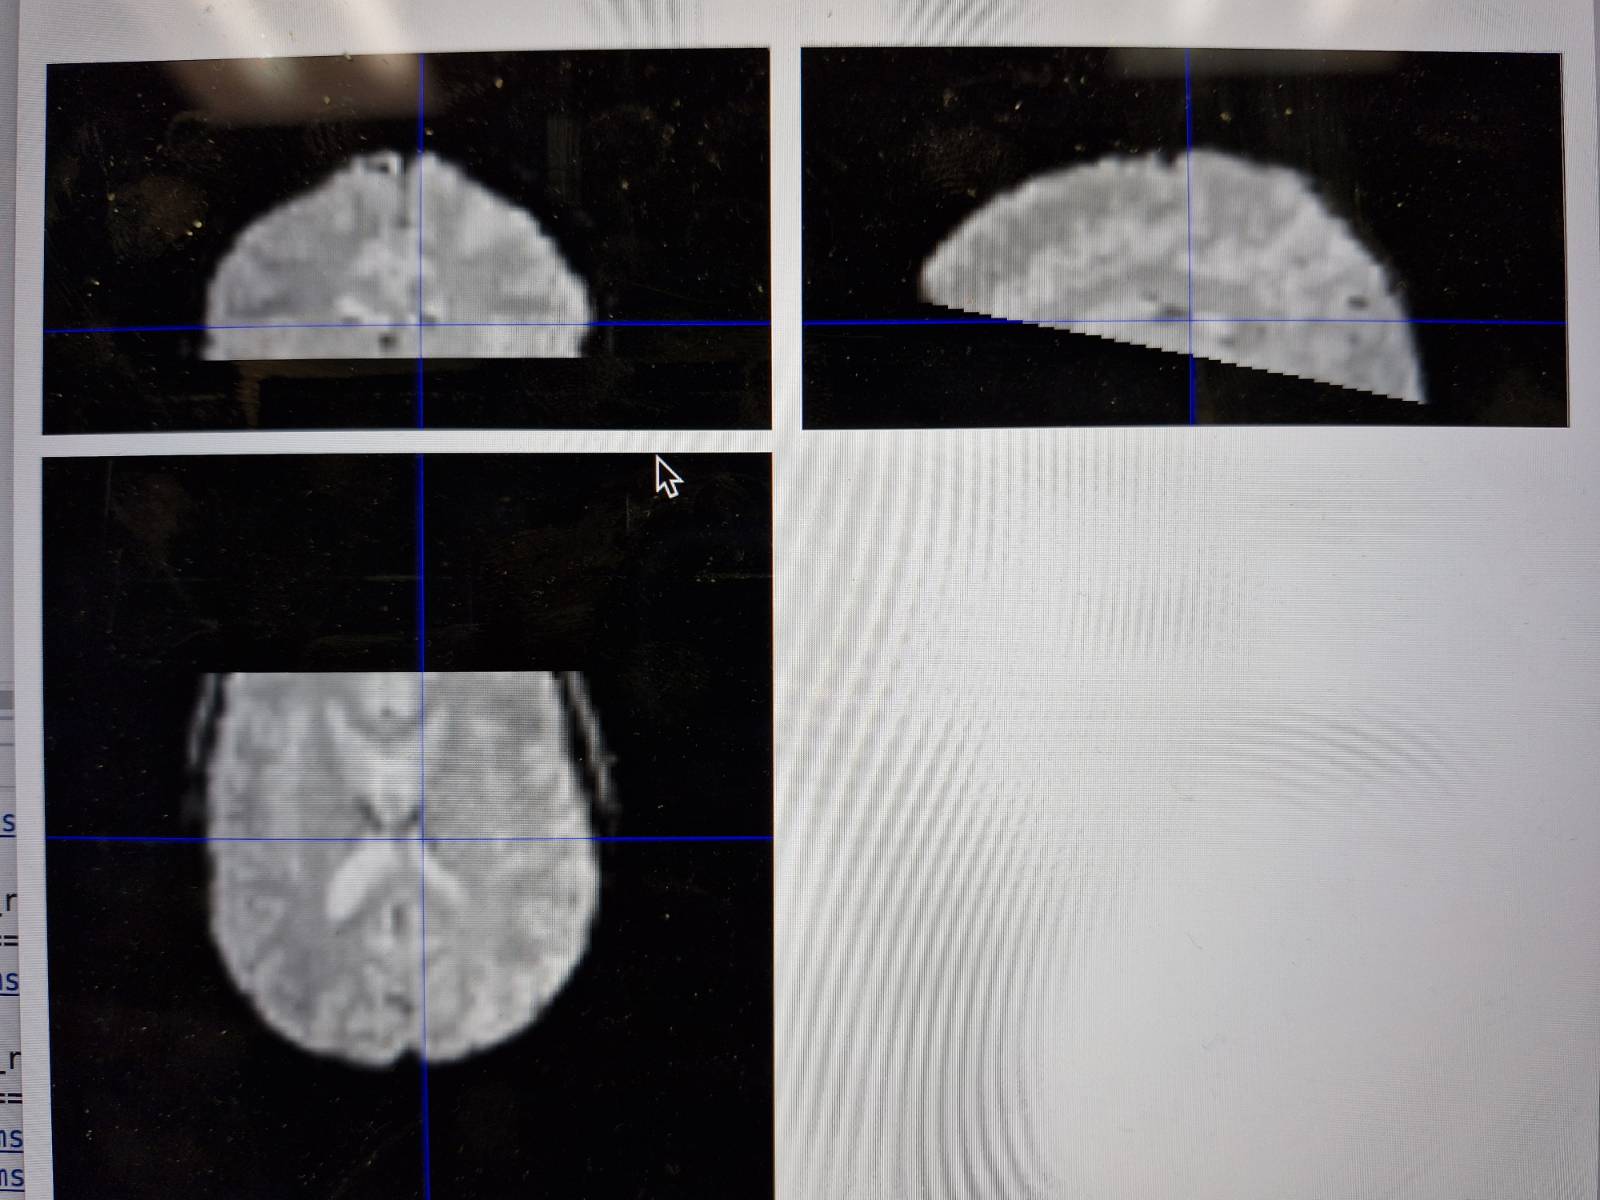

When I use the MRIcroGL to convert files into nii, I got a cropped image (image attached). What could it be?

In both cases, the image of the run_01(02)_bold appears cropped.